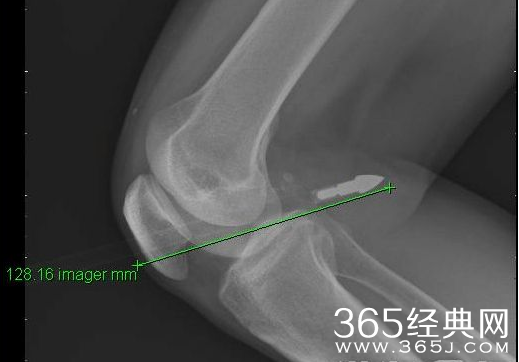

箭头射进膝盖内,留在外面的箭身足有70—80CM长。

明枪易躲暗箭难防,家住长沙井湾子51岁的王先生可算是体会这句话了,他在晾衣服时被一只飞来的利箭射伤了膝盖,金属箭头穿透膝盖足有12CM,被家人紧急送往长沙市中心医院抢救。1月19日,潇湘晨报记者从长沙市中心医院获悉,经紧急手术才及时将箭头取出,目前王先生正在留院观察中。

回想起自己被箭射伤的那一幕,王先生至今还心有余悸。王先生家住在井湾子某小区1楼,1月17日中午12时30分许,才吃完午饭的他到小区外晾衣服,谁知却被一只飞来的利箭所伤,箭头射进膝盖内,留在外面的箭身足有70—80CM长。“我当时背对着射箭的人,也没注意到他什么时候射的箭。”